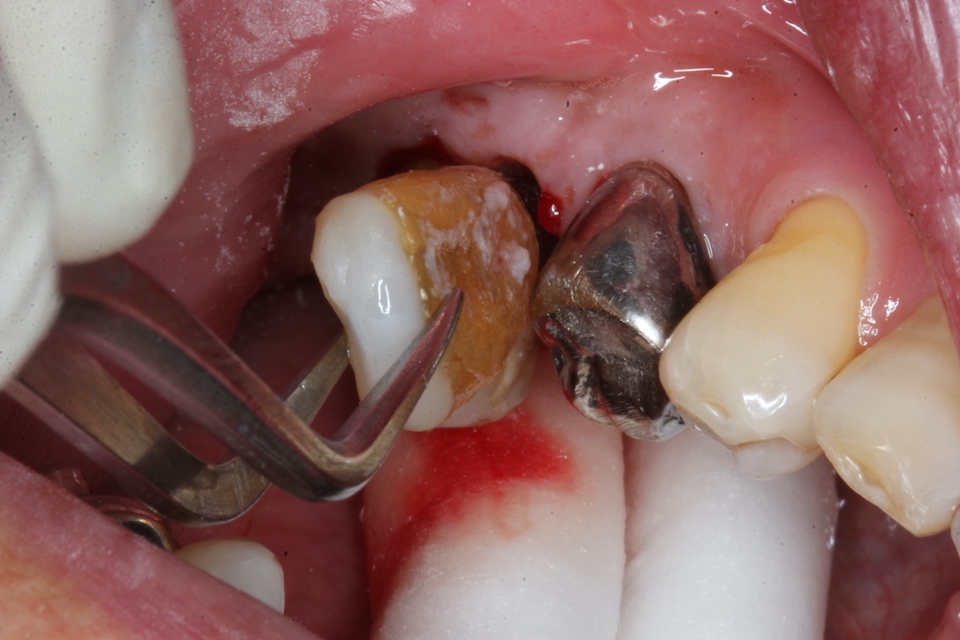

70代男性、左下7、歯根破折、自発痛++

今日は破折した歯根の接着面を新鮮面を出しきれいにしてスーパーボンドの筆積み法で貼り合わせポストを入れてCR併用で再建し、抜歯窩に挿入固定するだけだ。

以下時系列でどうぞ

根管充填材と歯質との間には隙間が存在し、細菌の代謝産物の黒色物質のFeSで覆われている。緊密な充填など絵に描いた餅にすぎない。

遠心根の切断面もスーパーボンド+CRで覆っておく